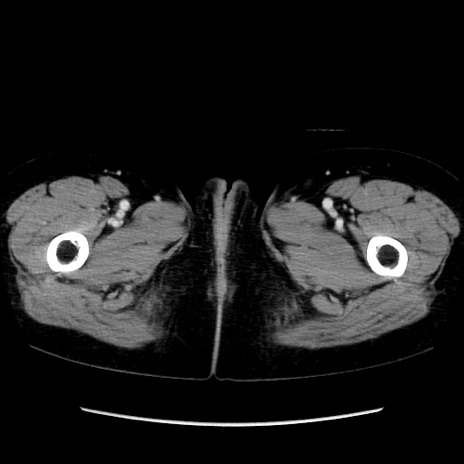

矢状断像

【症例】40歳代 女性

【主訴】上腹部痛、嘔気・嘔吐

【現病歴】約9時間前頃から急に上腹部痛、嘔気、嘔吐が出現。改善しないため救急要請。

【既往歴】子宮頚癌(広汎子宮全摘術、放射線療法)、腸閉塞

【身体所見】腹部:平坦、軟、腸雑音亢進、上腹部を中心に腹部全体に圧痛あり。

【データ】WBC 8400、CRP 0.03